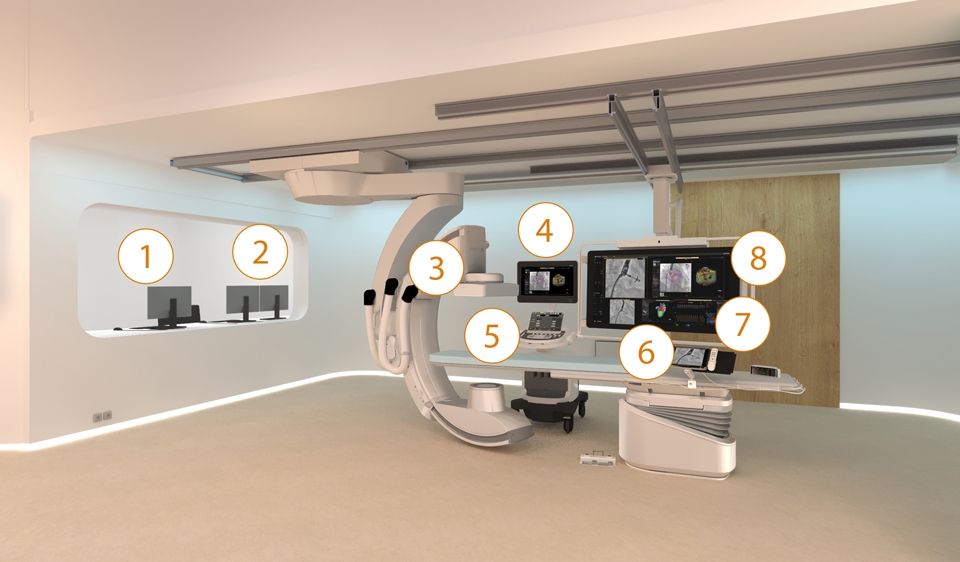

Image Guided Therapy System—Azurion

Azurion provides the ability to treat one more patient per day, reducing procedure time by 17%* with optimized workflow options in interventional therapy and clinical software. *Reducing procedure time by 17%, with the ability to treat 1 more patient per day with optimized workflow options in image guided therapy and clinical software (Azurion - Philips Azurion Simulation Study 2016 - 12NC 452299123041 - FEB 2017). Results are specific to the institution where they were obtained and may not reflect the results achievable at other institutions.